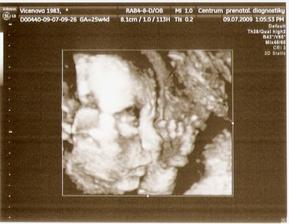

9.7. - 3D UTZ - vše ok, malá měla pořád ručičku před obličejíkem, takže zepředu se nám moc neukázala, ale z profilu ano, má špičatou bradičku :o) a váží 780 g :o)